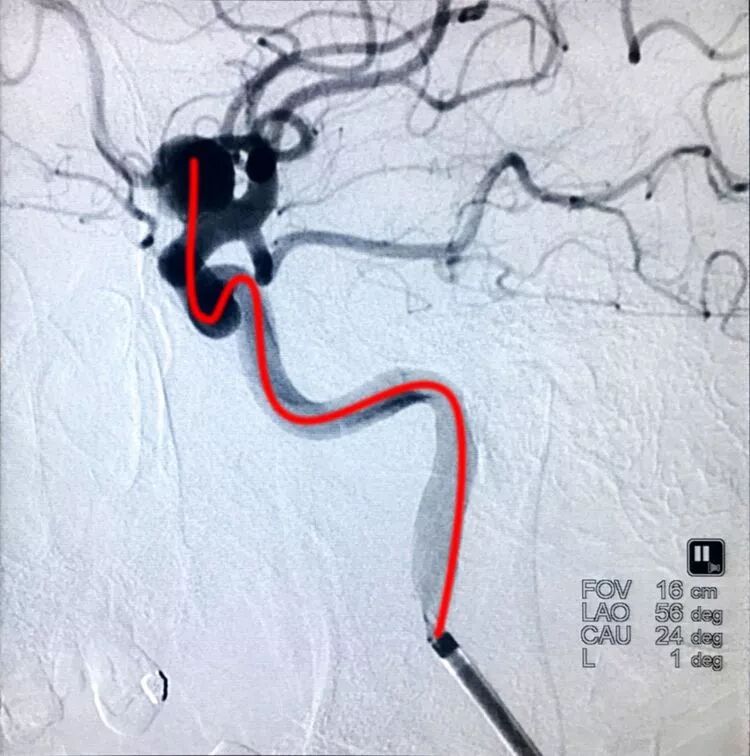

扁平状的前交通动脉瘤

仍然用双微管技术栓塞,一根直头微导管进入瘤体上部,另一根微导管头端塑成C形进入瘤体下部,分区栓塞该瘤